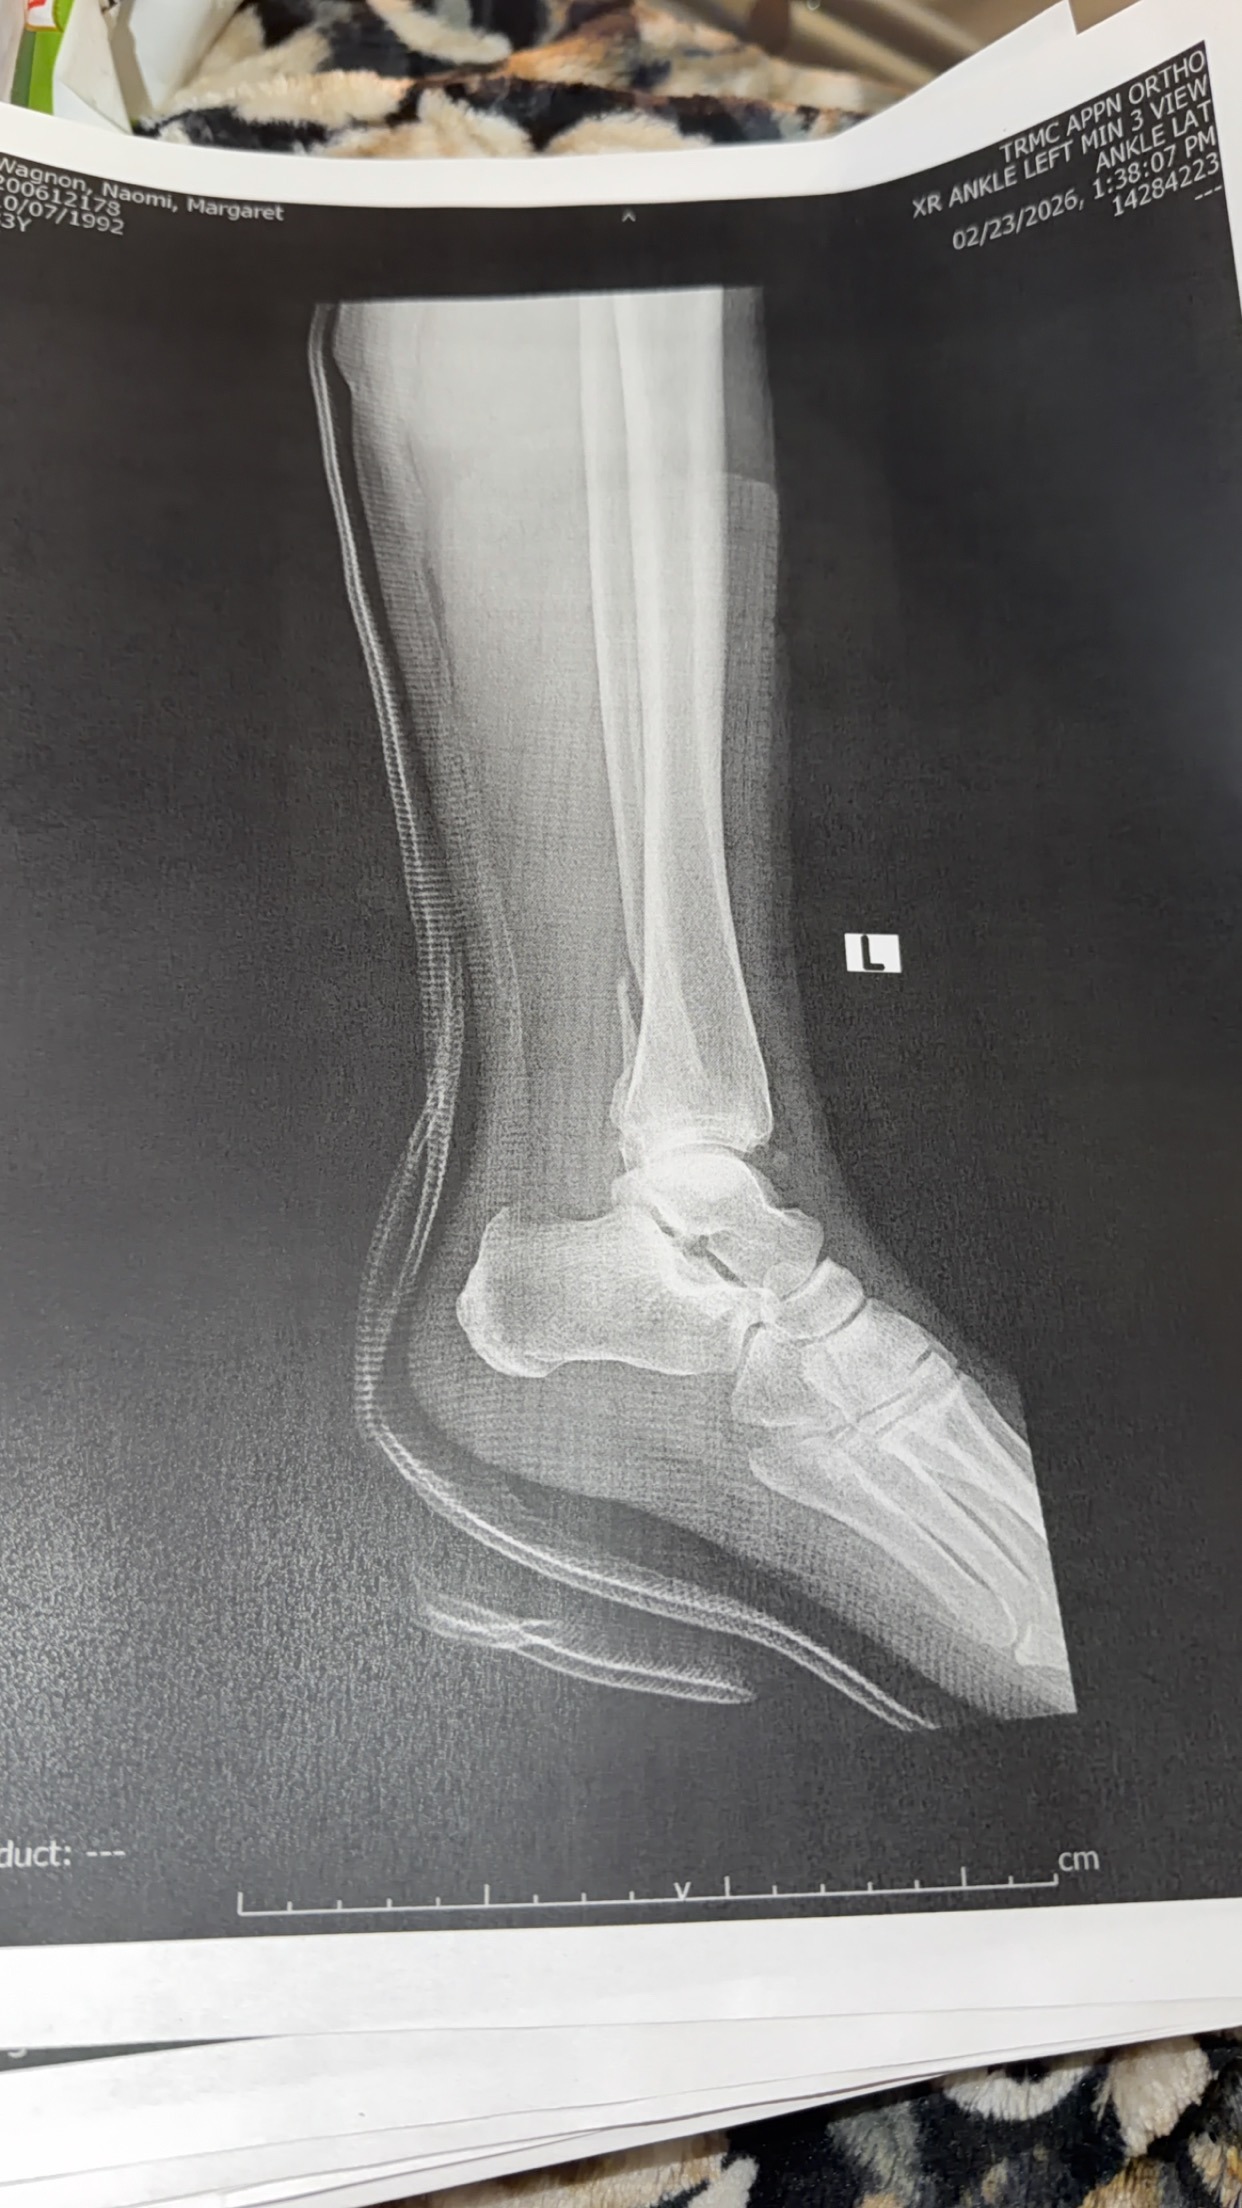

During the first significant snowfall in southern Oregon, Naomi slipped on her front steps and suffered a severe injury—breaking her ankle in multiple places, tearing tendons, and dislocating the joint. She underwent surgery within a week and is now on the long road to recovery. As a mother, it’s heartbreaking to see her in pain and facing so many challenges all at once.